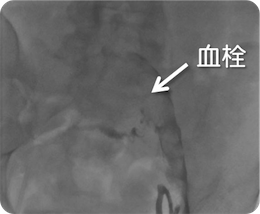

治療前

治療後

両側腸骨動脈の血栓閉塞に対するカテーテル治療

両下肢の疼痛、冷感、運動障害にて入院し緊急カテーテル検査を施行。 両側腸骨動脈に多量の血栓を認め、カテーテル血栓吸引療法を行い即座に血流を再開させました。